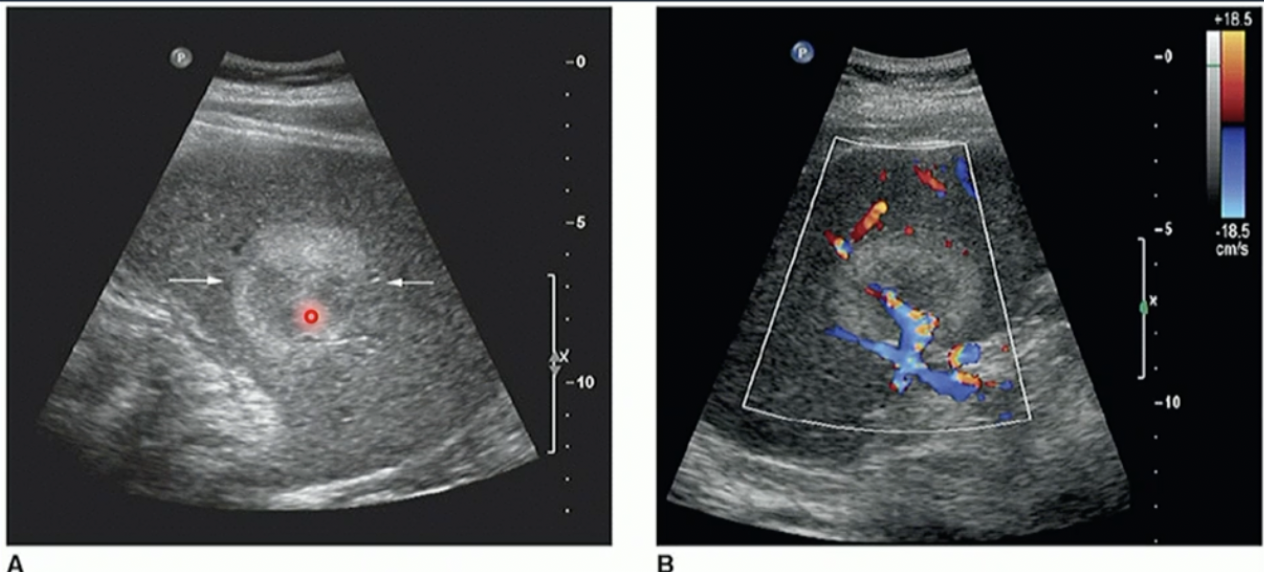

Difference between Haemangioma + HCC

Haemangioma has no blood vessels/lack of

HCC has blood vessels/blood flow

Pathology?

Haemangioma (due to no colour on it)

HCC due to colour/bloodflow